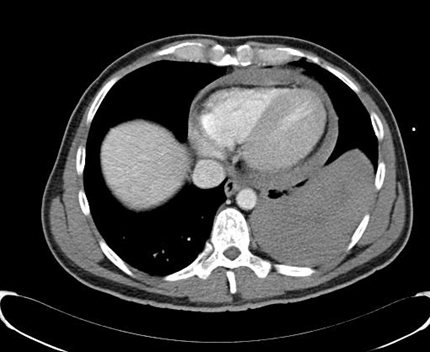

Two patients (42- and 49-year-old) were admitted to our emergency department after a suicide attempt. In the first case, the patient stabbed himself in the left chest with a letter opener. In the second case, the 49-year-old man shot himself with a 45-magnum-revolver into the anterior left chest wall. The clinical examination showed rarely bleeding thoracic wounds (Figure 1 [Fig. 1], Figure 2 [Fig. 2]). The patients were responsive, completely oriented (GCS=15) and hemodynamically stable. The abdominal sonography (FAST) showed no free fluid. Due to unclear injury patterns, a CT scan was performed. Shortly after the completion of the investigation, the patients became hemodynamically unstable with upper venous congestion. The patients were immediately transported to the operating room. In both cases, the computed-assisted tomography verified a massive left hematothorax and a pericardial tamponade (Figure 3 [Fig. 3], Figure 4 [Fig. 4]). In the case of the 42-year-old patient, a sternotomy was performed initially, followed by an anterolateral thoracotomy to supply the intercostal vessels more sufficiently. The second patient was treated with a left anterolateral thoracotomy. In both cases, a blood-filled pleural cavity, a lesion of the left ventricle as due to the pericardial tamponade and extracardiac injuries were found (Table 1 [Tab. 1]).

Figure 3: Computer-assisted tomography: hematothorax

Figure 4: Computer-assisted tomography: pericardial tamponade